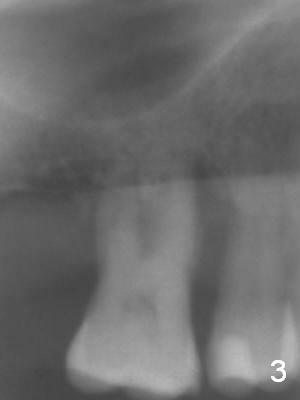

A 44-year-old man requests an implant at #3 because of mobility. It appears that the bone height decreases from 6 mm (Fig.1,2: 3 years ago) to 4 mm (Fig.3,4, recently). After extraction and Clindamycin treatment, take PVS impression of the socket. Use initial drill with drill stopper of 3 mm and round burs with stoppers from 4 to 5 mm. If the buccal (B) and palatal (P) plate defect is severe, use a regular implant. Otherwise use an extra wide one. The advantage of the latter is length as short as 6 mm vs. 8 mm for the regular one. For the latter, 2 mm of the implant will be in the sinus (Fig.4 red box), 4 mm in bone (pink box) and 2 mm in the socket (orange box; to be surrounded by bone graft). Since the gingiva is 6 mm (Fig.4 green box), an abutment with 6 mm cuff should be chosen. To reduce occlusal interference, select abutment height 4 mm.

Recently periodontal abscess occurs with purulent discharge from the buccal sulcus (Fig.5 *) and palatal gingiva erythema and edema (Fig.6 *). The buccal and palatal plates are most likely defective. A small diameter implant should be placed. The infection at #3 may be the cause of failure of implant at #31 (redo).